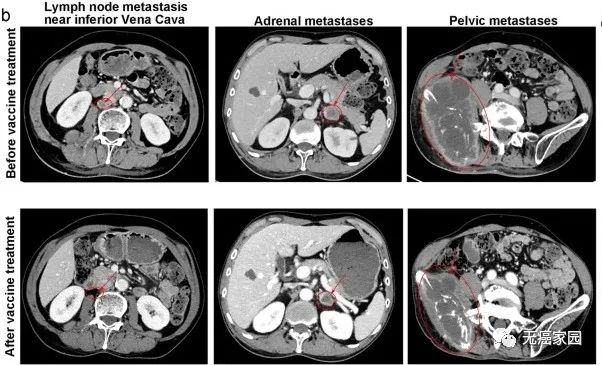

图中患者靠近下腔静脉的转移瘤基本消失,肾上腺转移及盆腔巨大转移灶明显缩小对于复发性晚期癌症患者,这种联合疗法可以发挥抗肿瘤的作用,而且不会增加毒性及副作用。Deo-DCVac疫苗是安全和有效的,并适用于晚期肺癌患者。